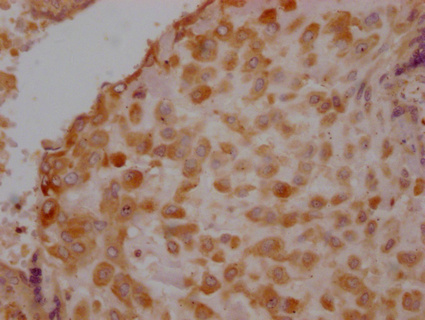

IHC image of CSB-PA751229LA01HU diluted at 1:100 and staining in paraffin-embedded human placenta tissue performed on a Leica BondTM system. After dewaxing and hydration, antigen retrieval was mediated by high pressure in a citrate buffer (pH 6.0). Section was blocked with 10% normal goat serum 30min at RT. Then primary antibody (1% BSA) was incubated at 4°C overnight. The primary is detected by a Goat anti-rabbit IgG polymer labeled by HRP and visualized using 0.05% DAB.